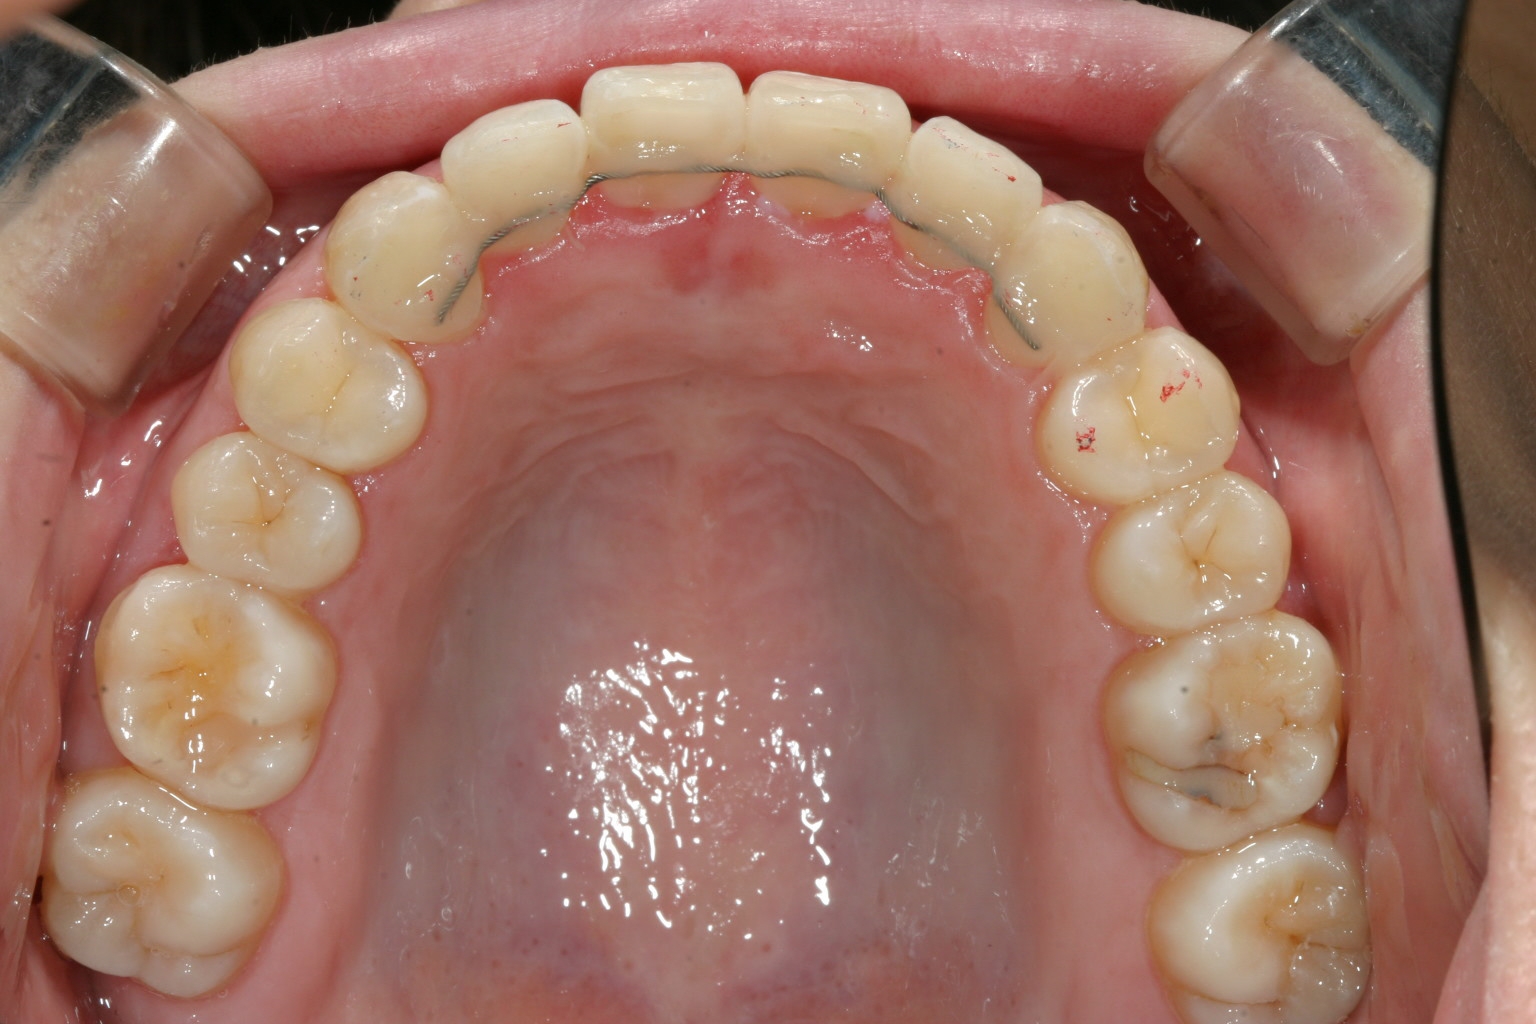

綺麗に改善しています。

下顎の叢生も綺麗に改善しています。

オーバーバイトも抜群です。